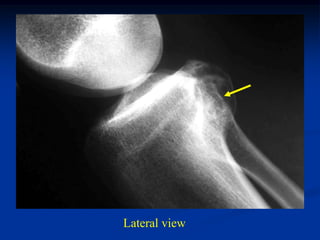

Case #556

55 year male with

enchondroma tibia

Lateral view